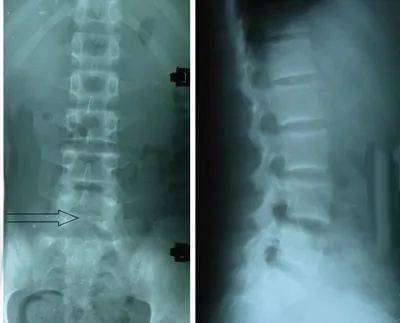

椎体隐裂

椎体隐裂,隐裂腰椎

第五腰椎的隐性裂,腰椎骶化

骶椎隐裂是什么鬼?能治好吗?

隐性脊柱裂的人群发生率约在3/1000左右.